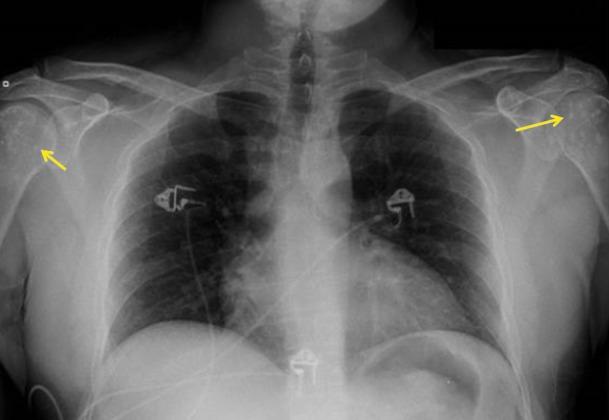

Osteopoikilosis is a rare condition that is characterized by multiple small non-aggressive appearing sclerotic foci in a periarticular distribution. Typically, it does not cause any symptoms and is diagnosed incidentally on imaging studies done for other reasons. We present a case of osteopoikilosis in a 37-year-old male, which was diagnosed incidentally on radiographs.